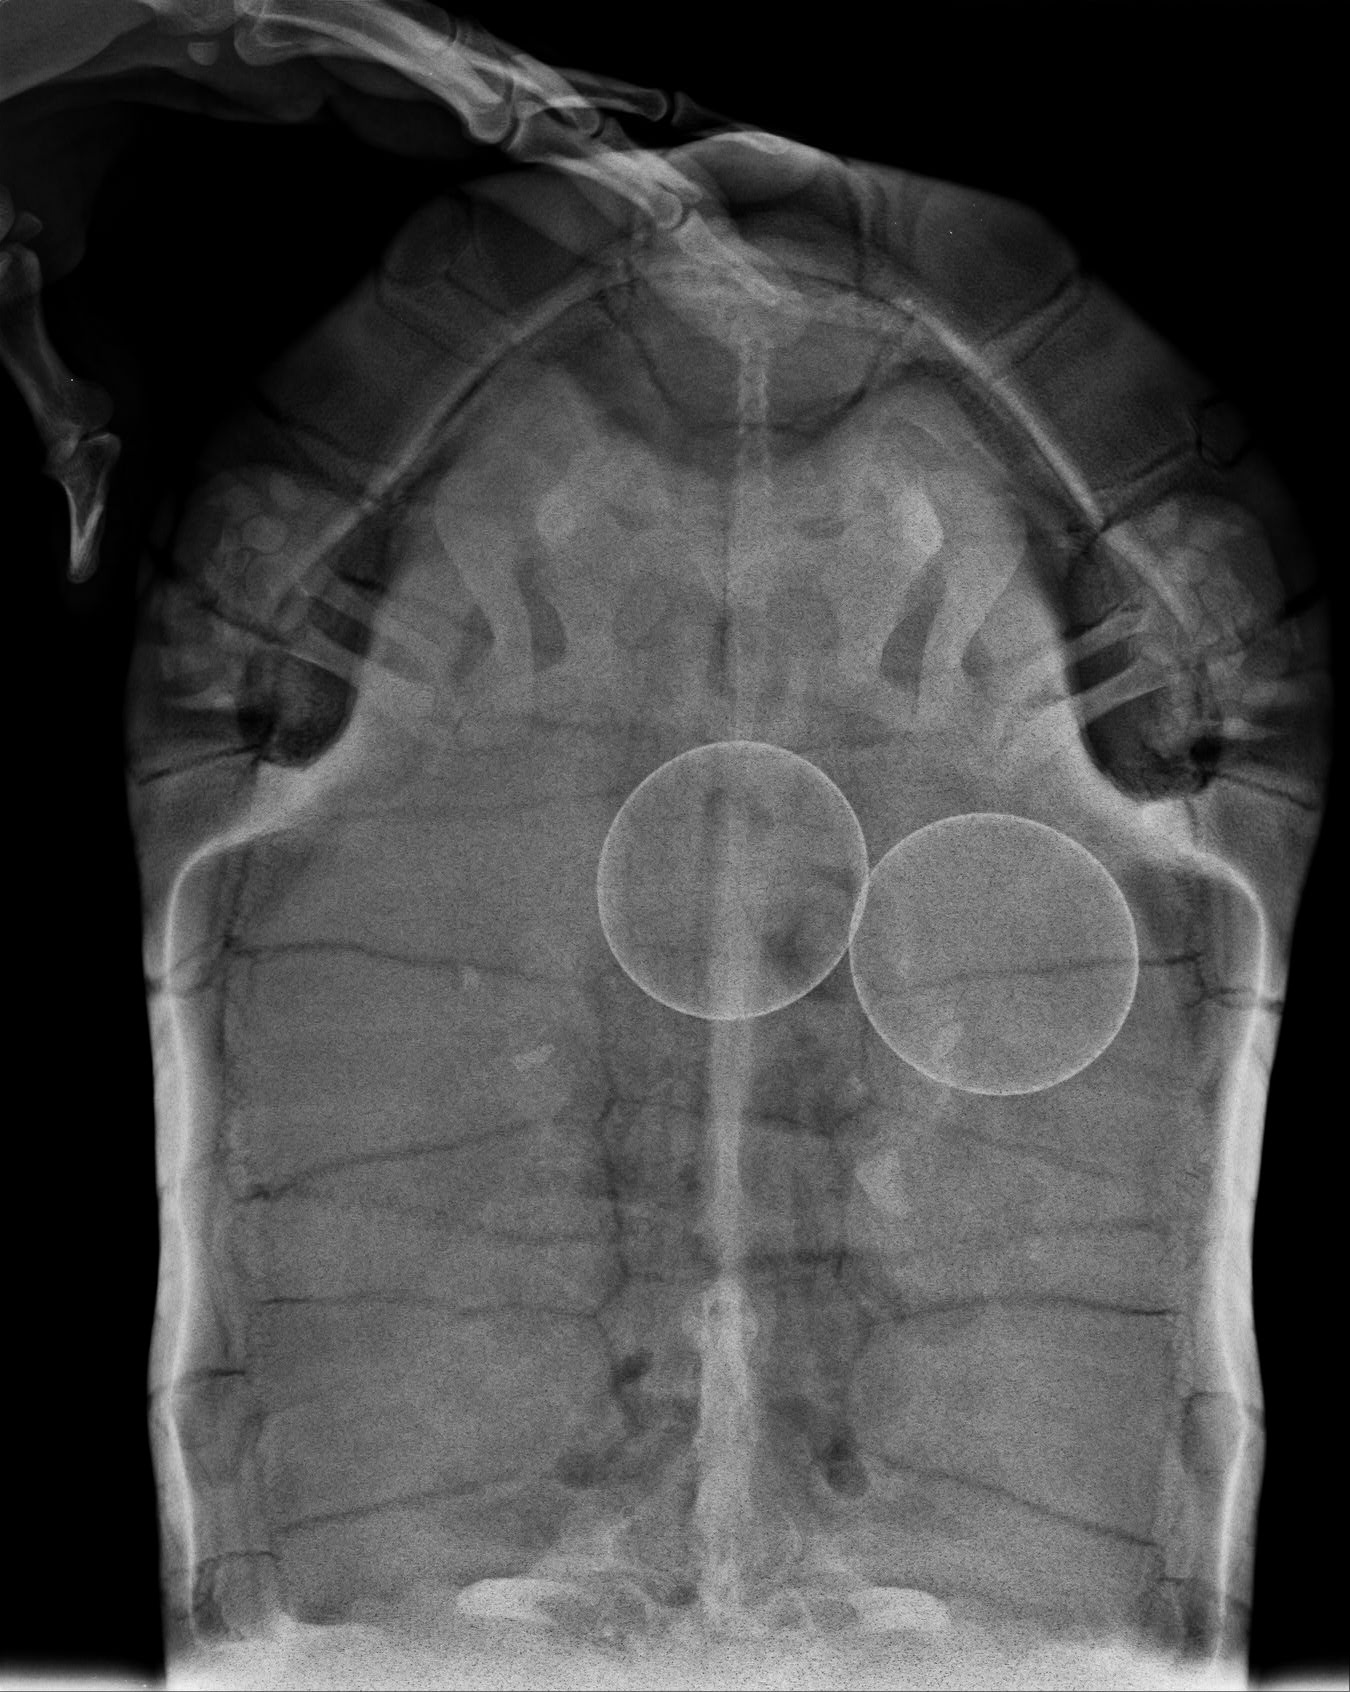

doporucuji navstivit veterinare, ktery se vyzna plazech. Pred nekolika lety jsme meli podobnou situaci s zelvou zelenavou (Testudo hermanni). Na rengenu se zjistilo uviznuti vajicka v mocovodu (pokud si spravne vzpominam, kazdopadne to bylo mimo obvykle cesty) a zbytneni vajecniku. Zelva podstoupila operaci, pri niz bylo nutne rozriznout spodni cast krunyre a vyndat zadrzenou snusku vcetne vajecniku, vyoperovanych vajec v ruznych stadiich vyvoje byla plna hrst. Zelva se zotavila bez problemu a dari se ji vyborne, jinak by zrejme zahynula.

Děkuji za radu , už jsem o tom taky uvažoval a tak jsem dnes navštívil veterinu a vypadá to vše v pohodě.Jenom dvě vajíčka a tam kde mají být.